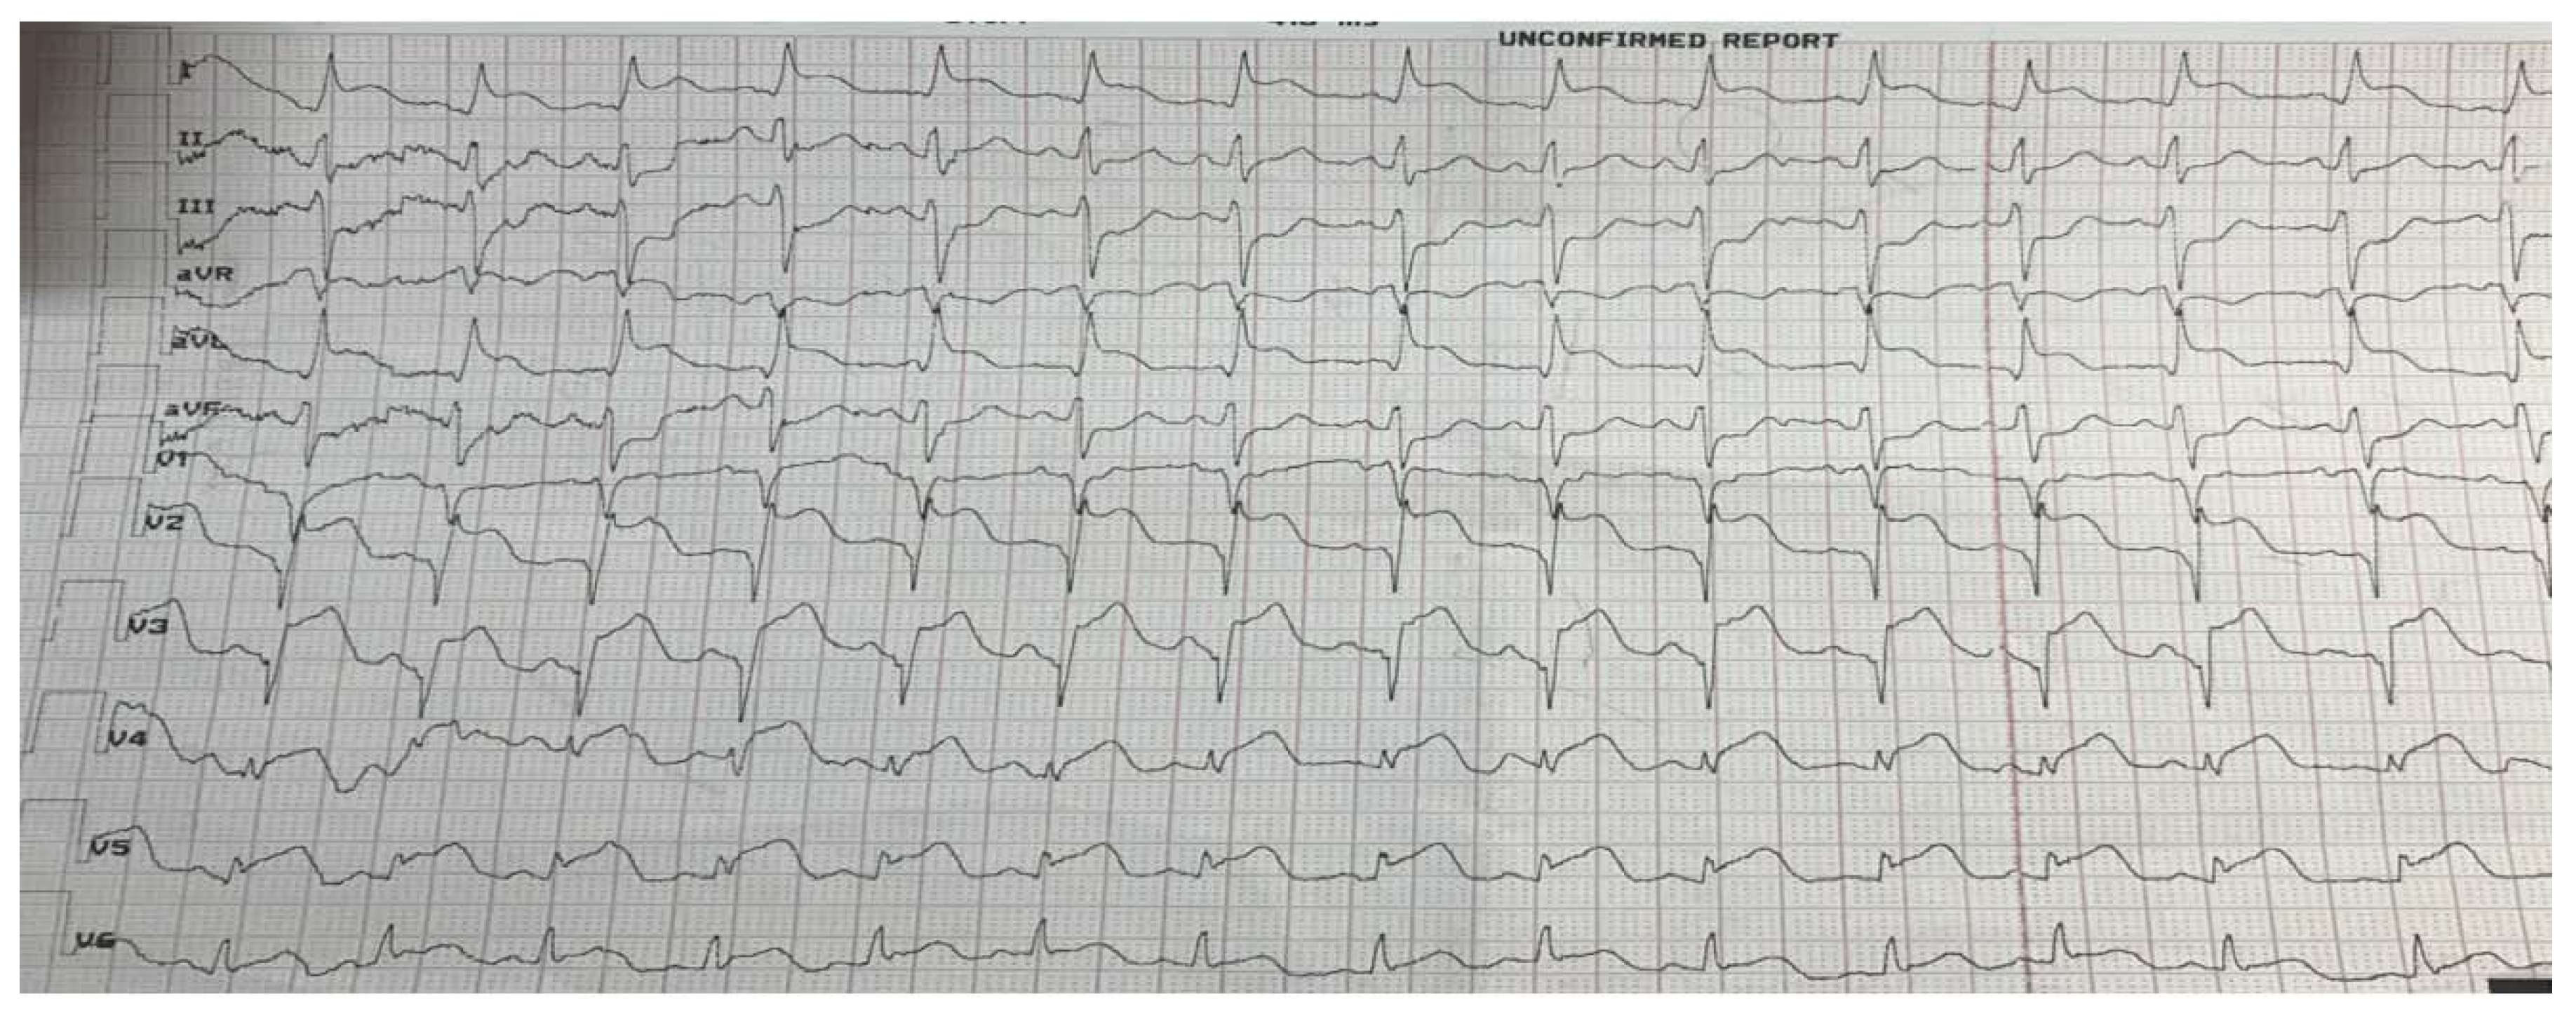

The obstetric examination showed aligned cervix with 2 cm to 3 cm dilation and regular heartbeats in the neonate. DAPT consisting of aspirin 300 mg and ticagrelor 180 mg, with the support of inotropic drugs, was administered. Angiography disclosed a 90% diameter stenosis in the proximal segment of the left anterior descendent coronary artery (LAD) and left coronary sinus aneurysm. Due to high thrombus burden, bolus eptifibatide was administered. (Figure 2a)

After diagnosing single-vessel disease, drug-eluting stent (DES, type: Premier® 3.0x28mm) was implanted in the osteo-proximal part of LAD (Figure 2b).

Figure 2. Coronary angiography: (a) stenosis of the proximal segment of left anterior descendent coronary artery (arrow). (b) recovery of coronary flow after stent implantation (arrow).